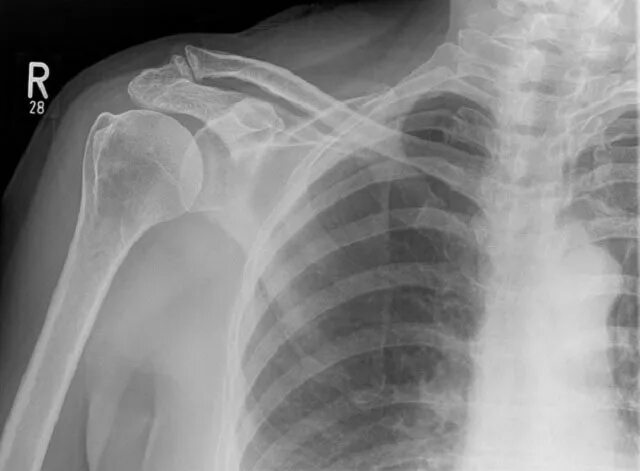

Артроз ключично акромиального сочленения плечевого